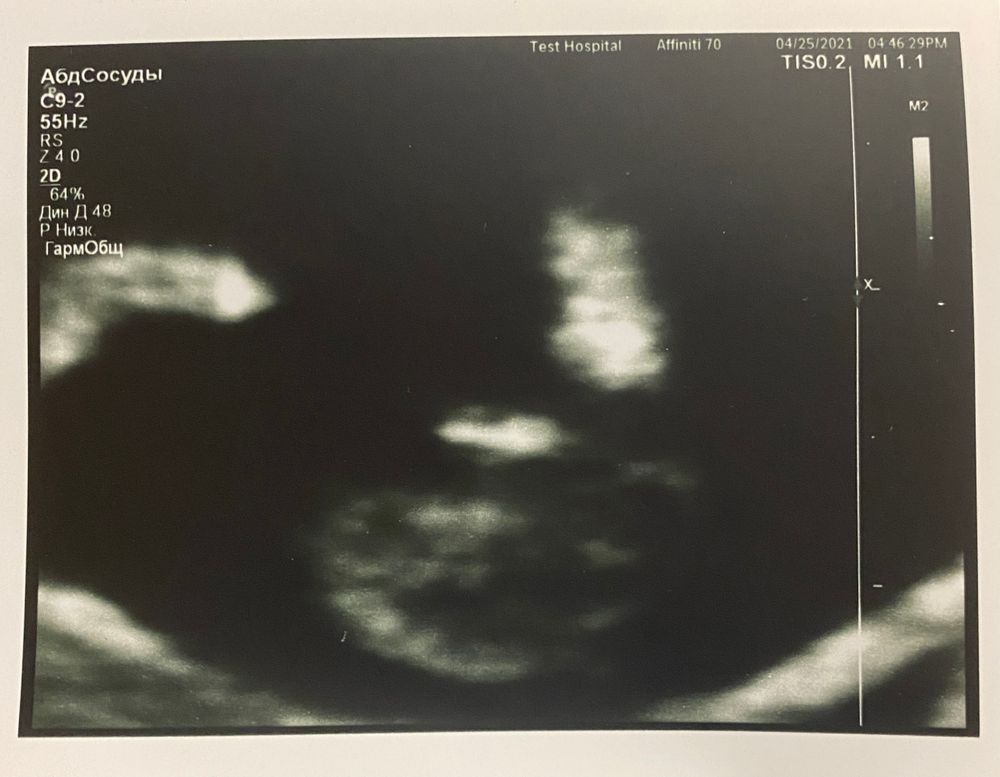

А дальше узист сказала, что это на 100% мальчик 🙈😁 что между ножек явно формируется писюн (на фотке ниже в самом центре) вот что то я сомневаюсь, неужели на таком сроке можно так точно определить? (Не по углу наклона, а просто по внешнему виду?) Как думаете?